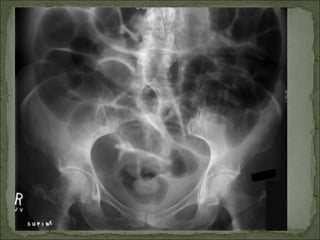

Dor em cólica; Distensão abdominal; Peristaltismo visível (ocasional); Desconforto à palpação; RHA aumentados em número e com alteração do timbre(metálico); Hipertimpanismo à percussão; Raio-X: distensão de alças com níveis hidroaéreos; Ex: obstrução de delgado (neoplasia, volvo, brida), cólica biliar ou renal

Dor em cólica;Distensão abdominal; Peristaltismo visível (ocasional); Desconforto à palpação; RHA aumentados em número e com alteração do timbre(metálico); Hipertimpanismo à percussão; Raio-X: distensão de alças com níveis hidroaéreos; Ex: obstrução de delgado (neoplasia, volvo, brida), cólica biliar ou renal